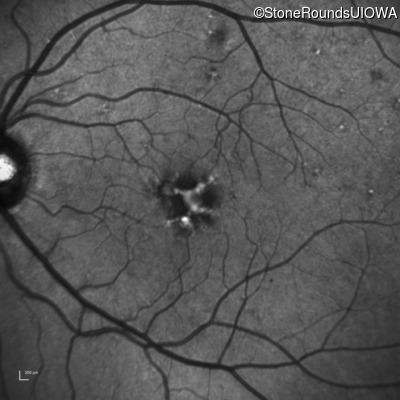

Infrared Fundus Photograph - Left - 20/25 +1 sc

Exemplar